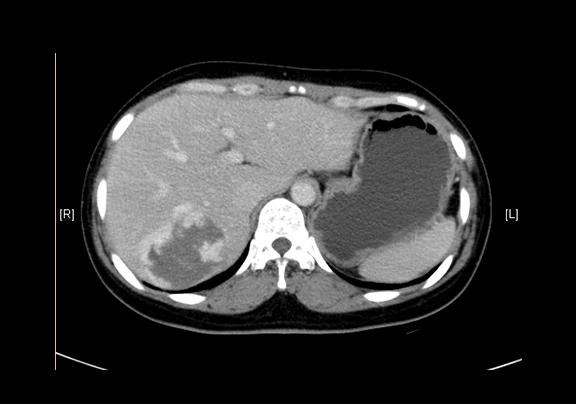

术前CT检查:动脉期